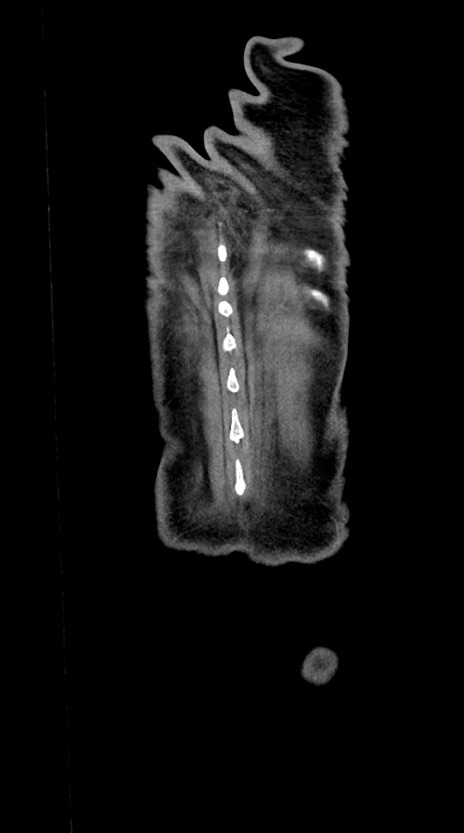

【症例】60歳代男性

【主訴】嘔吐

【現病歴】胃癌にて胃全摘後。食思不振が悪化し、夜中に嘔吐することがある。

【既往歴】胃癌、胃全摘、脾摘、胆摘後

【データ】WBC 5900、CRP 10.56